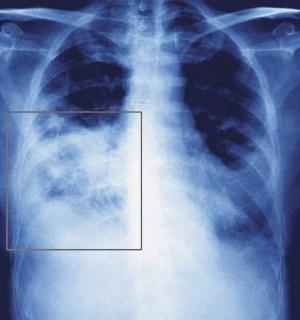

Plaušu karsonis ir smaga plaušu infekcijas slimība, kuru visbiežāk izraisa baktērijas pneimokoki, kas pastāvīgi atrodas uz elpceļu gļotādas. To aktivēšanos veicina saaukstēšanās, pārpūle, traumas, akūtas infekcijas. Slimībai ir raksturīgs klepus, nespēks, apgrūtināta elpošana, stipri paaugstināta temperatūra. Infekcija izraisa gļotu un strutu uzkrāšanos alveolās, tādējādi apgrūtinot gāzu maiņu.

Infekcijas perēkļus var saskatīt, veicot plaušu rentgenu. Specifiskā imunitāte neveidojas pret visām baktērijām, kas izraisa plaušu karsoni, tāpēc ar šo slimību var saslimt vairākkārt.